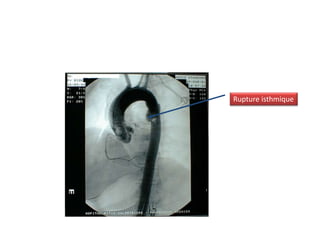

Rupture isthmique

ARTERIOGRAPHIE